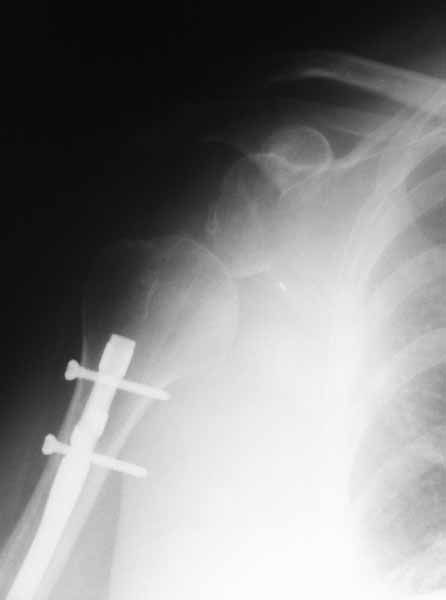

Плечевой сустав на сегодняший день спустя 10 мес. после травмы.